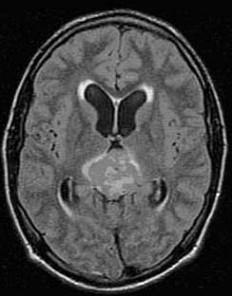

松果体区肿瘤(如图所示)的临床表现哪项不正确()A.女性病人性早熟B.尿崩症C.瞳孔对光反应和调节反应障碍D.水平眼球震颤E.上视障碍

问题 松果体区肿瘤(如图所示)的临床表现哪项不正确()

选项 A.女性病人性早熟 B.尿崩症 C.瞳孔对光反应和调节反应障碍 D.水平眼球震颤 E.上视障碍

答案 A